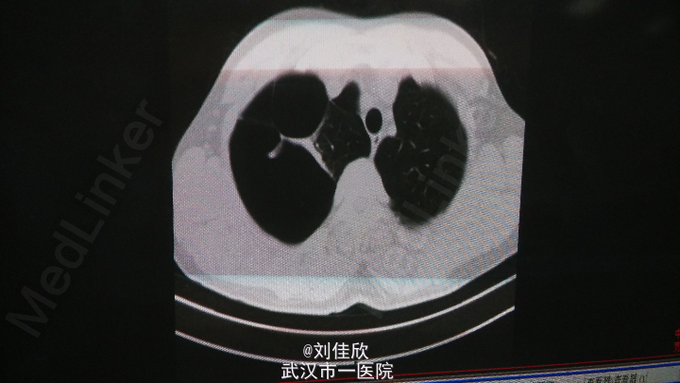

查体:右肺呼吸音低,余查体(-)。 辅助检查:当地医院胸片示:右肺肺大疱,右肺压缩约90%。6-10:肺、纵隔平扫:1.右肺大量气胸,肺组织压缩至纵隔旁呈三角形,肺组织压缩90%左右,右肺门影增大,建议复张后随访复查排除病变。2.右侧胸膜呈结节状或结片状增厚并部分胸膜粘连;3.右侧胸膜腔少量积液。4.左肺上叶及下叶胸膜下多发微小斑点状结节影,直径约1-2mm。(见下图)